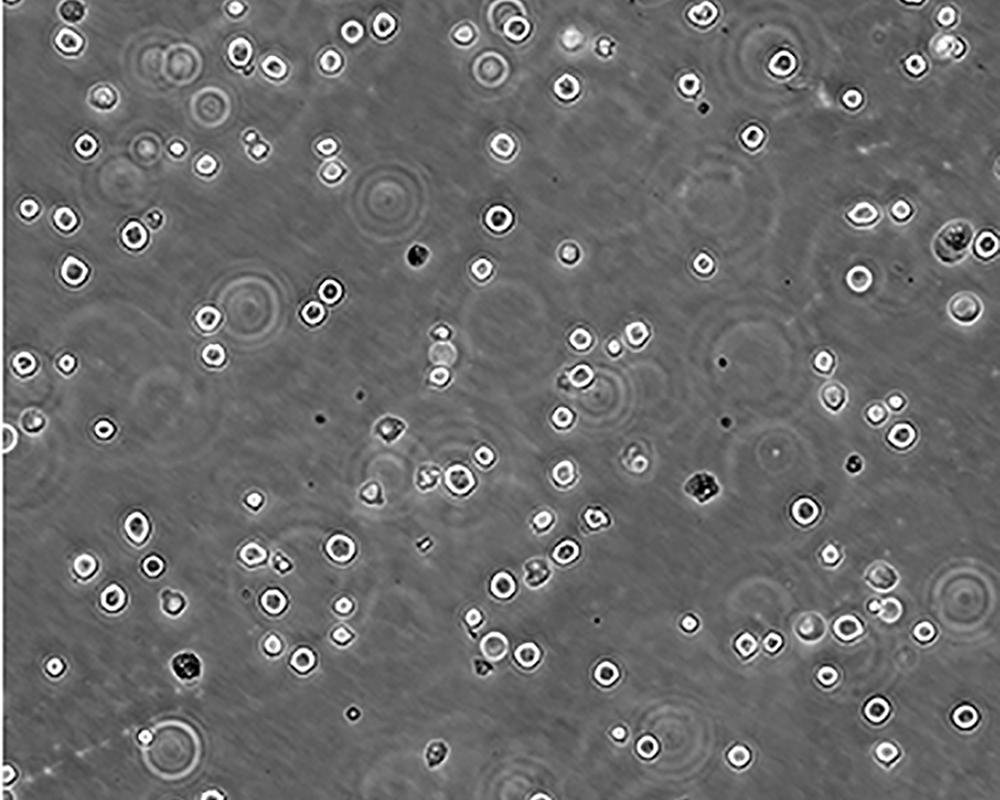

K-562 [K562]細(xì)胞

產(chǎn)品名稱 K-562 [K562]細(xì)胞

中文名稱 人慢性髓原白血病細(xì)胞

組織來源 慢性髓細(xì)胞白血病;女性

細(xì)胞種屬 Homo sapiens, human

生長(zhǎng)特性 suspension

培養(yǎng)基 IMDM+10% FBS+1% P/S

形態(tài)特征 lymphoblast

傳代方法 1:2-1:4

培養(yǎng)條件 Atmosphere: Air, 95%; CO2, 5%。Temperature: 37℃

細(xì)胞描述 The cell population has been characterized as highly undifferentiated and of the granulocytic series. Studies conducted by Anderson, et al. , on the surface membrane properties led to the conclusion that the K-562 was a human erythroleukemia line. K-562 blasts are multipotential, hematopoietic malignant cells that spontaneously differentiate into recognizable progenitors of the erythrocytic, granulocytic and monocytic series. The effect of inducers on sublines derived from the original K-562 cell line have been reviewed by Koeffler and Golde. Karyological studies on various K- 562 sublines have been classified into three groups(A,B,C) by Dimery, et al. The strain obtained by the ATCC most closely resembles the B population. Occurrence of the Philadelphia chromosome, however, was of much lower frequency; none detected in 15 metaphases examined. The line is EBNA negative.

細(xì)胞凍存 Freeze medium: 50% basal medium+40% FBS+10%.DMSOStorage temperature: liquid nitrogen vapor phase

細(xì)胞運(yùn)輸 干冰運(yùn)輸(2ml凍存管)或活細(xì)胞運(yùn)輸(T25細(xì)胞瓶)